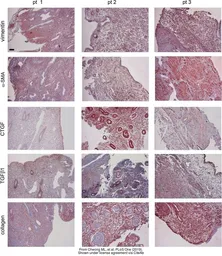

The data was published in the journal PLoS One in 2019. PMID: 30695033

The data was published in the journal Front Pharmacol in 2016. PMID: 27199755